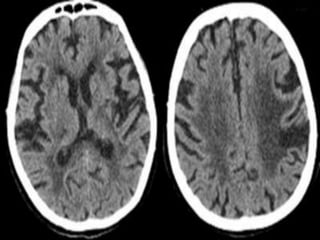

Which one is CT brain

How to differentiate CT from MRI

• Bone is dense(white) on CT brain while hypo

intense(dark) on MRI(outer bright signals on

MRI are due to subcutaneous fats).

• Grey-white matter differentiation is clear on

MRI compared to the CT.

• Presence of periventricular lucent areas in

MRI.

• MRI usually have multiple films compared to

commonly single in CT